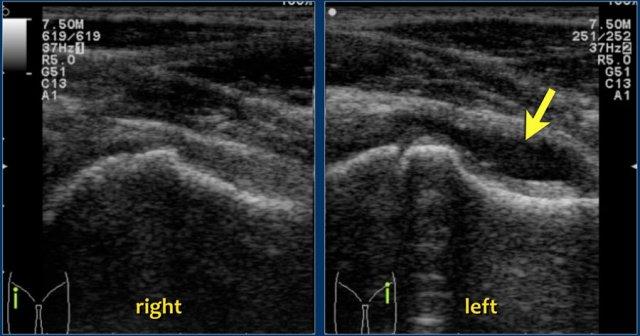

Viêm màng hoạt dịch thoáng qua. Khớp háng trái cho thấy tràn dịch khớp (mũi tên) ở túi cùng trước gây tách các lớp bao khớp, hiện có thể nhận diện rõ ràng

Chẩn đoán hình ảnh không thực sự cần thiết, nhưng siêu âm thường được chỉ định để xác nhận sự hiện diện của tràn dịch khớp.

Đặc điểm hình ảnh của dịch tràn trên siêu âm không có giá trị trong chẩn đoán phân biệt.